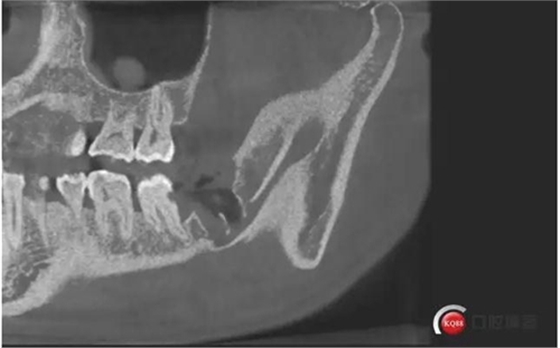

下面CBCT,可以看到兩個(gè)牙根的根尖三分之一在神經(jīng)管里面。

CBCT神經(jīng)管標(biāo)線,可以看到標(biāo)線不能連續(xù),中間被阻斷。